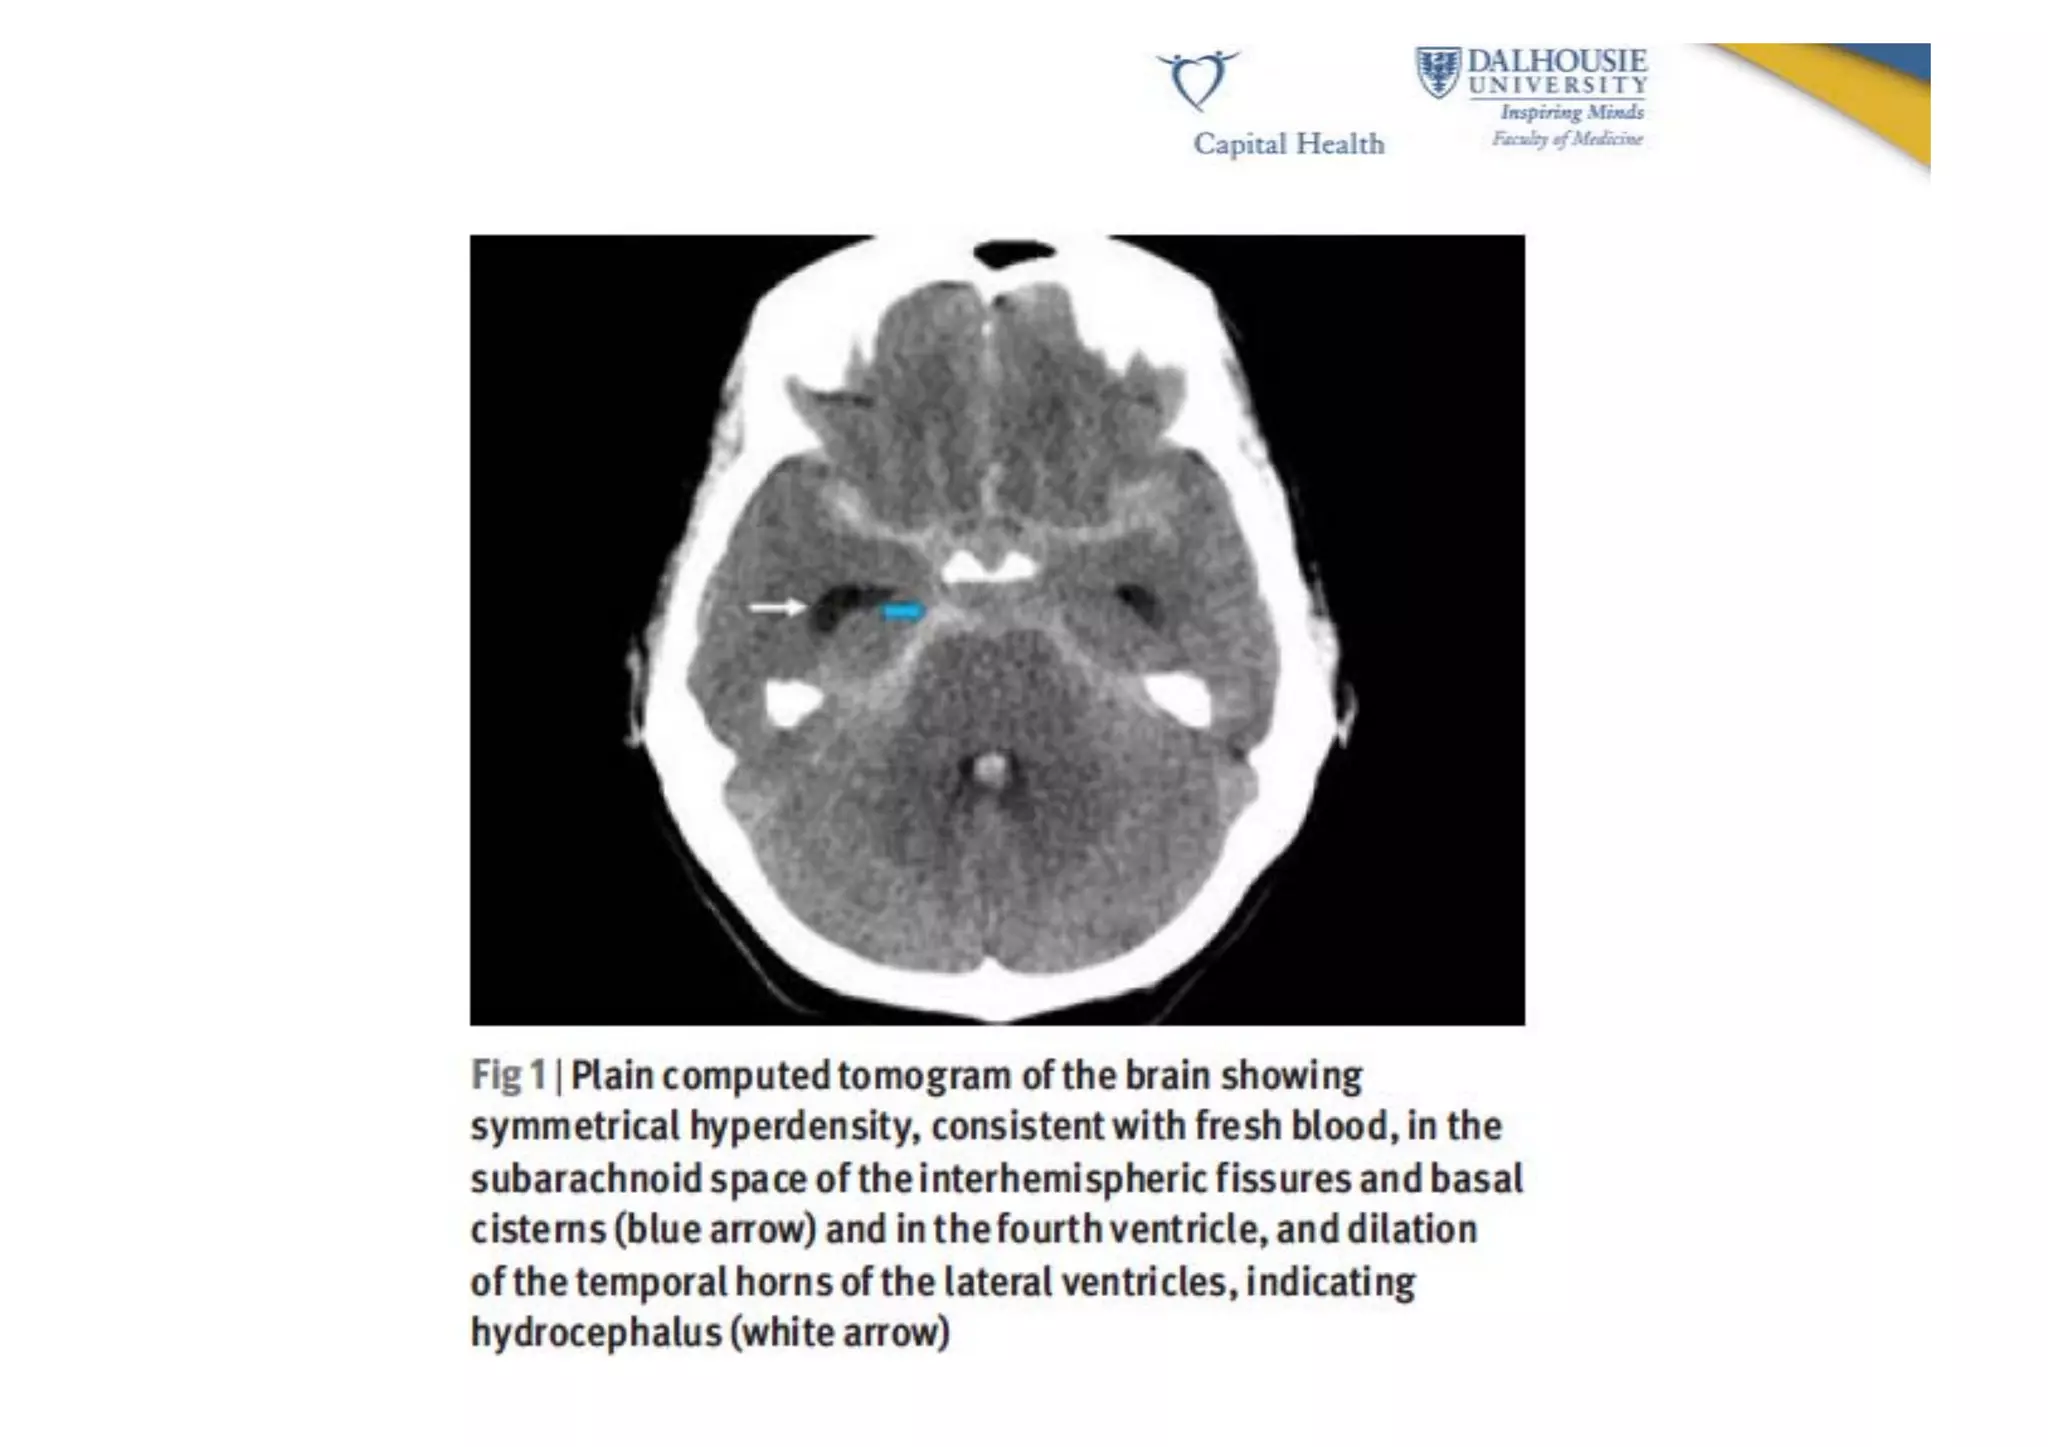

Diagnosis   •  CT  scan  AND  lumbar  puncture  if  scan  is  nega9ve   •  If  SAH  is  found,  it  is  usually  followed  with   catheter  cerebral  angio  or  MR/CT  angio  to   document  the  anatomic  features   •  CT  scan  detects  93-­‐98%  of  SAH